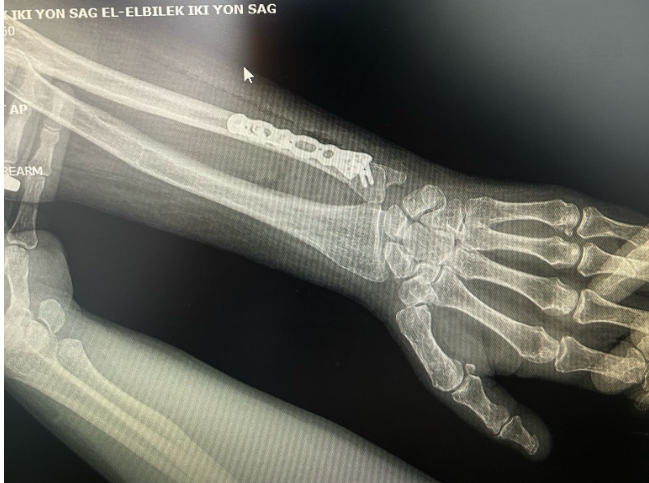

Önkol kırık ameliyatı

Ön Kol kırık ameliyatı